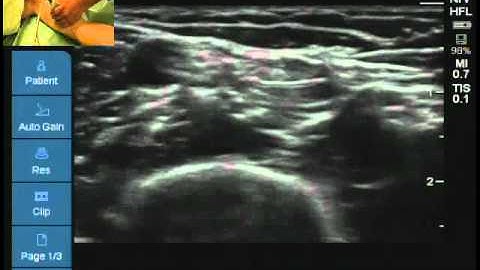

Locating the axillary nerve